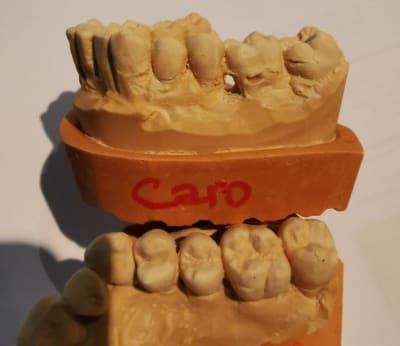

modèles de départ, photos avec le téléphone, désolé, mais ça donne une petite idée

--